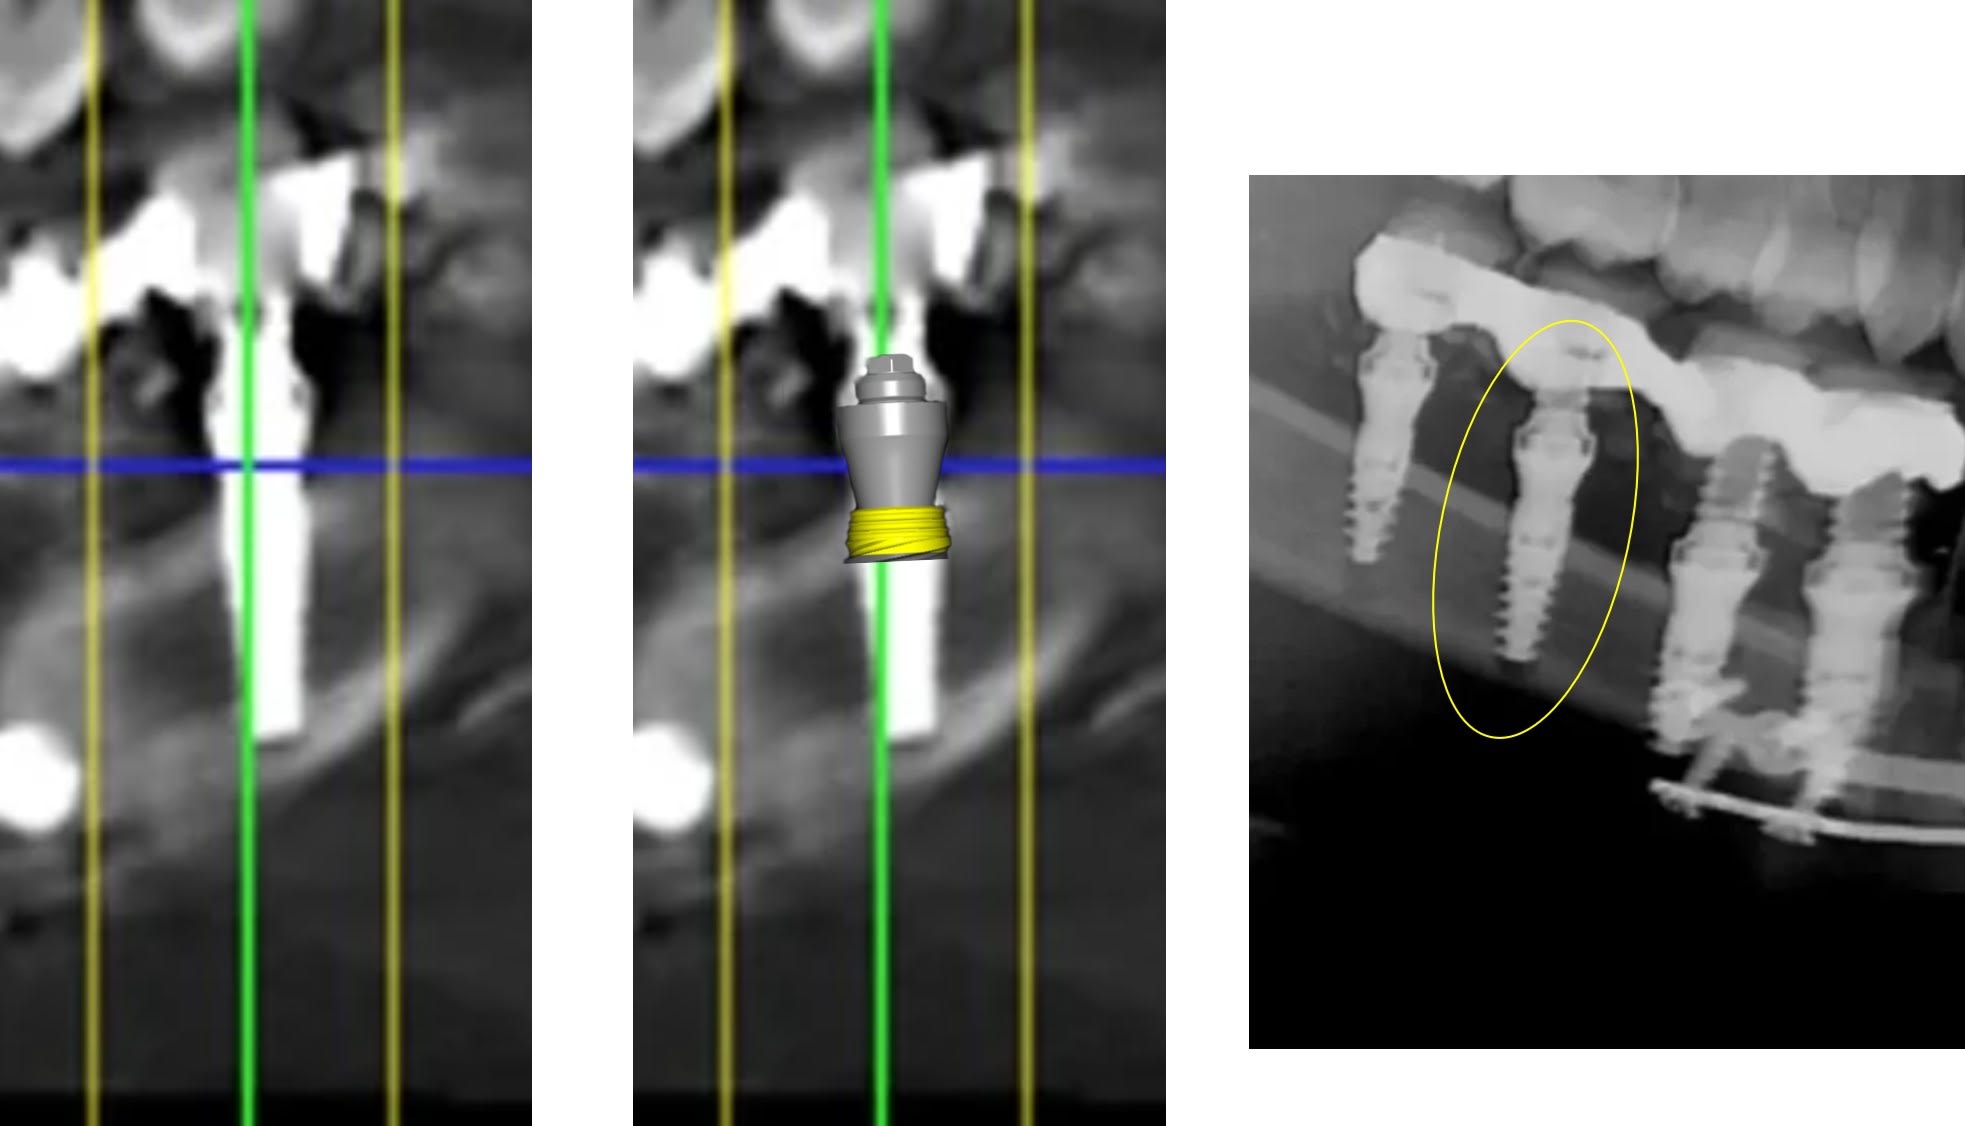

a parce qu il faut etre expert pour voir que les deux derniers implants sont clairement pas dans l os ??

1 se baser sur la pano pour en tirer des conclusions est une erreur de débutant

2 sur les coupes scanner une partie du col est infra osseuse et l'autre non

3 lorsque tu te permets le genre de commentaire que tu fais il faut être en mesure d'étayer un argumentaire

mais posit... y'a que toi qui pense que l'implant est aussi enfoui... ca saute aux yeux que tu fais tout pour grater 1mm d'enfouissement... pour qu'ils paraissent pas si mal posé que ca...

avec, par exemple, ton implant de 10mm qui est contenu dans 9mm... t'es le Gérard Majax des guides chir.

comme ici... si e carré fait 4,5 alors l’implant ne fait pas 10 mais moins de 9...

Tout comme l’autre implant pas 11,5 mais 10,3

heureusement que ta méthode est "précise" ;)

Pour le reste de la discussion que le col ne soit tout infra osseux oui mais pas "5 spires" et tout les implants sont en bi corticale. Lorsque tu dis à quelqu'un qu'il est de mauvaise foi vérifie en premier tes arguments. Pour le col dans un cas comme celui là ce n'est pas un problème.